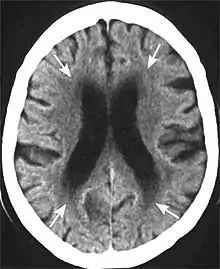

Head CT showing periventricular white matter lesions.

Leukoaraiosis is a particular abnormal change in appearance of white matter near the lateral ventricles. It is often seen in aged individuals, but sometimes in young adults.[1][2] On MRI, leukoaraiosis changes appear as white matter hyperintensities (WMHs) in T2 FLAIR images.[3][4] On CT scans, leukoaraiosis appears as hypodense periventricular white-matter lesions.[5]

These white matter changes are also commonly referred to as periventricular white matter disease, or white matter hyperintensities (WMH), due to their bright white appearance on T2 MRI scans. Many patients can have leukoaraiosis without any associated clinical abnormality. However, underlying vascular mechanisms are suspected to be the cause of the imaging findings. Hypertension, smoking, diabetes,[3] hyperhomocysteinemia, and heart diseases are all risk factors for leukoaraiosis.